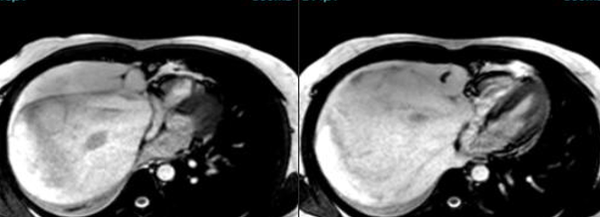

Cardiac MRI is a useful tool to diagnose amyloidosis. T1 mapping has become a mainstay, both native and ECV measurements. ECV measurement can now help quantify the amyloidosis burden and may help guide treatment based on how the ECV responds to specific treatment measures.